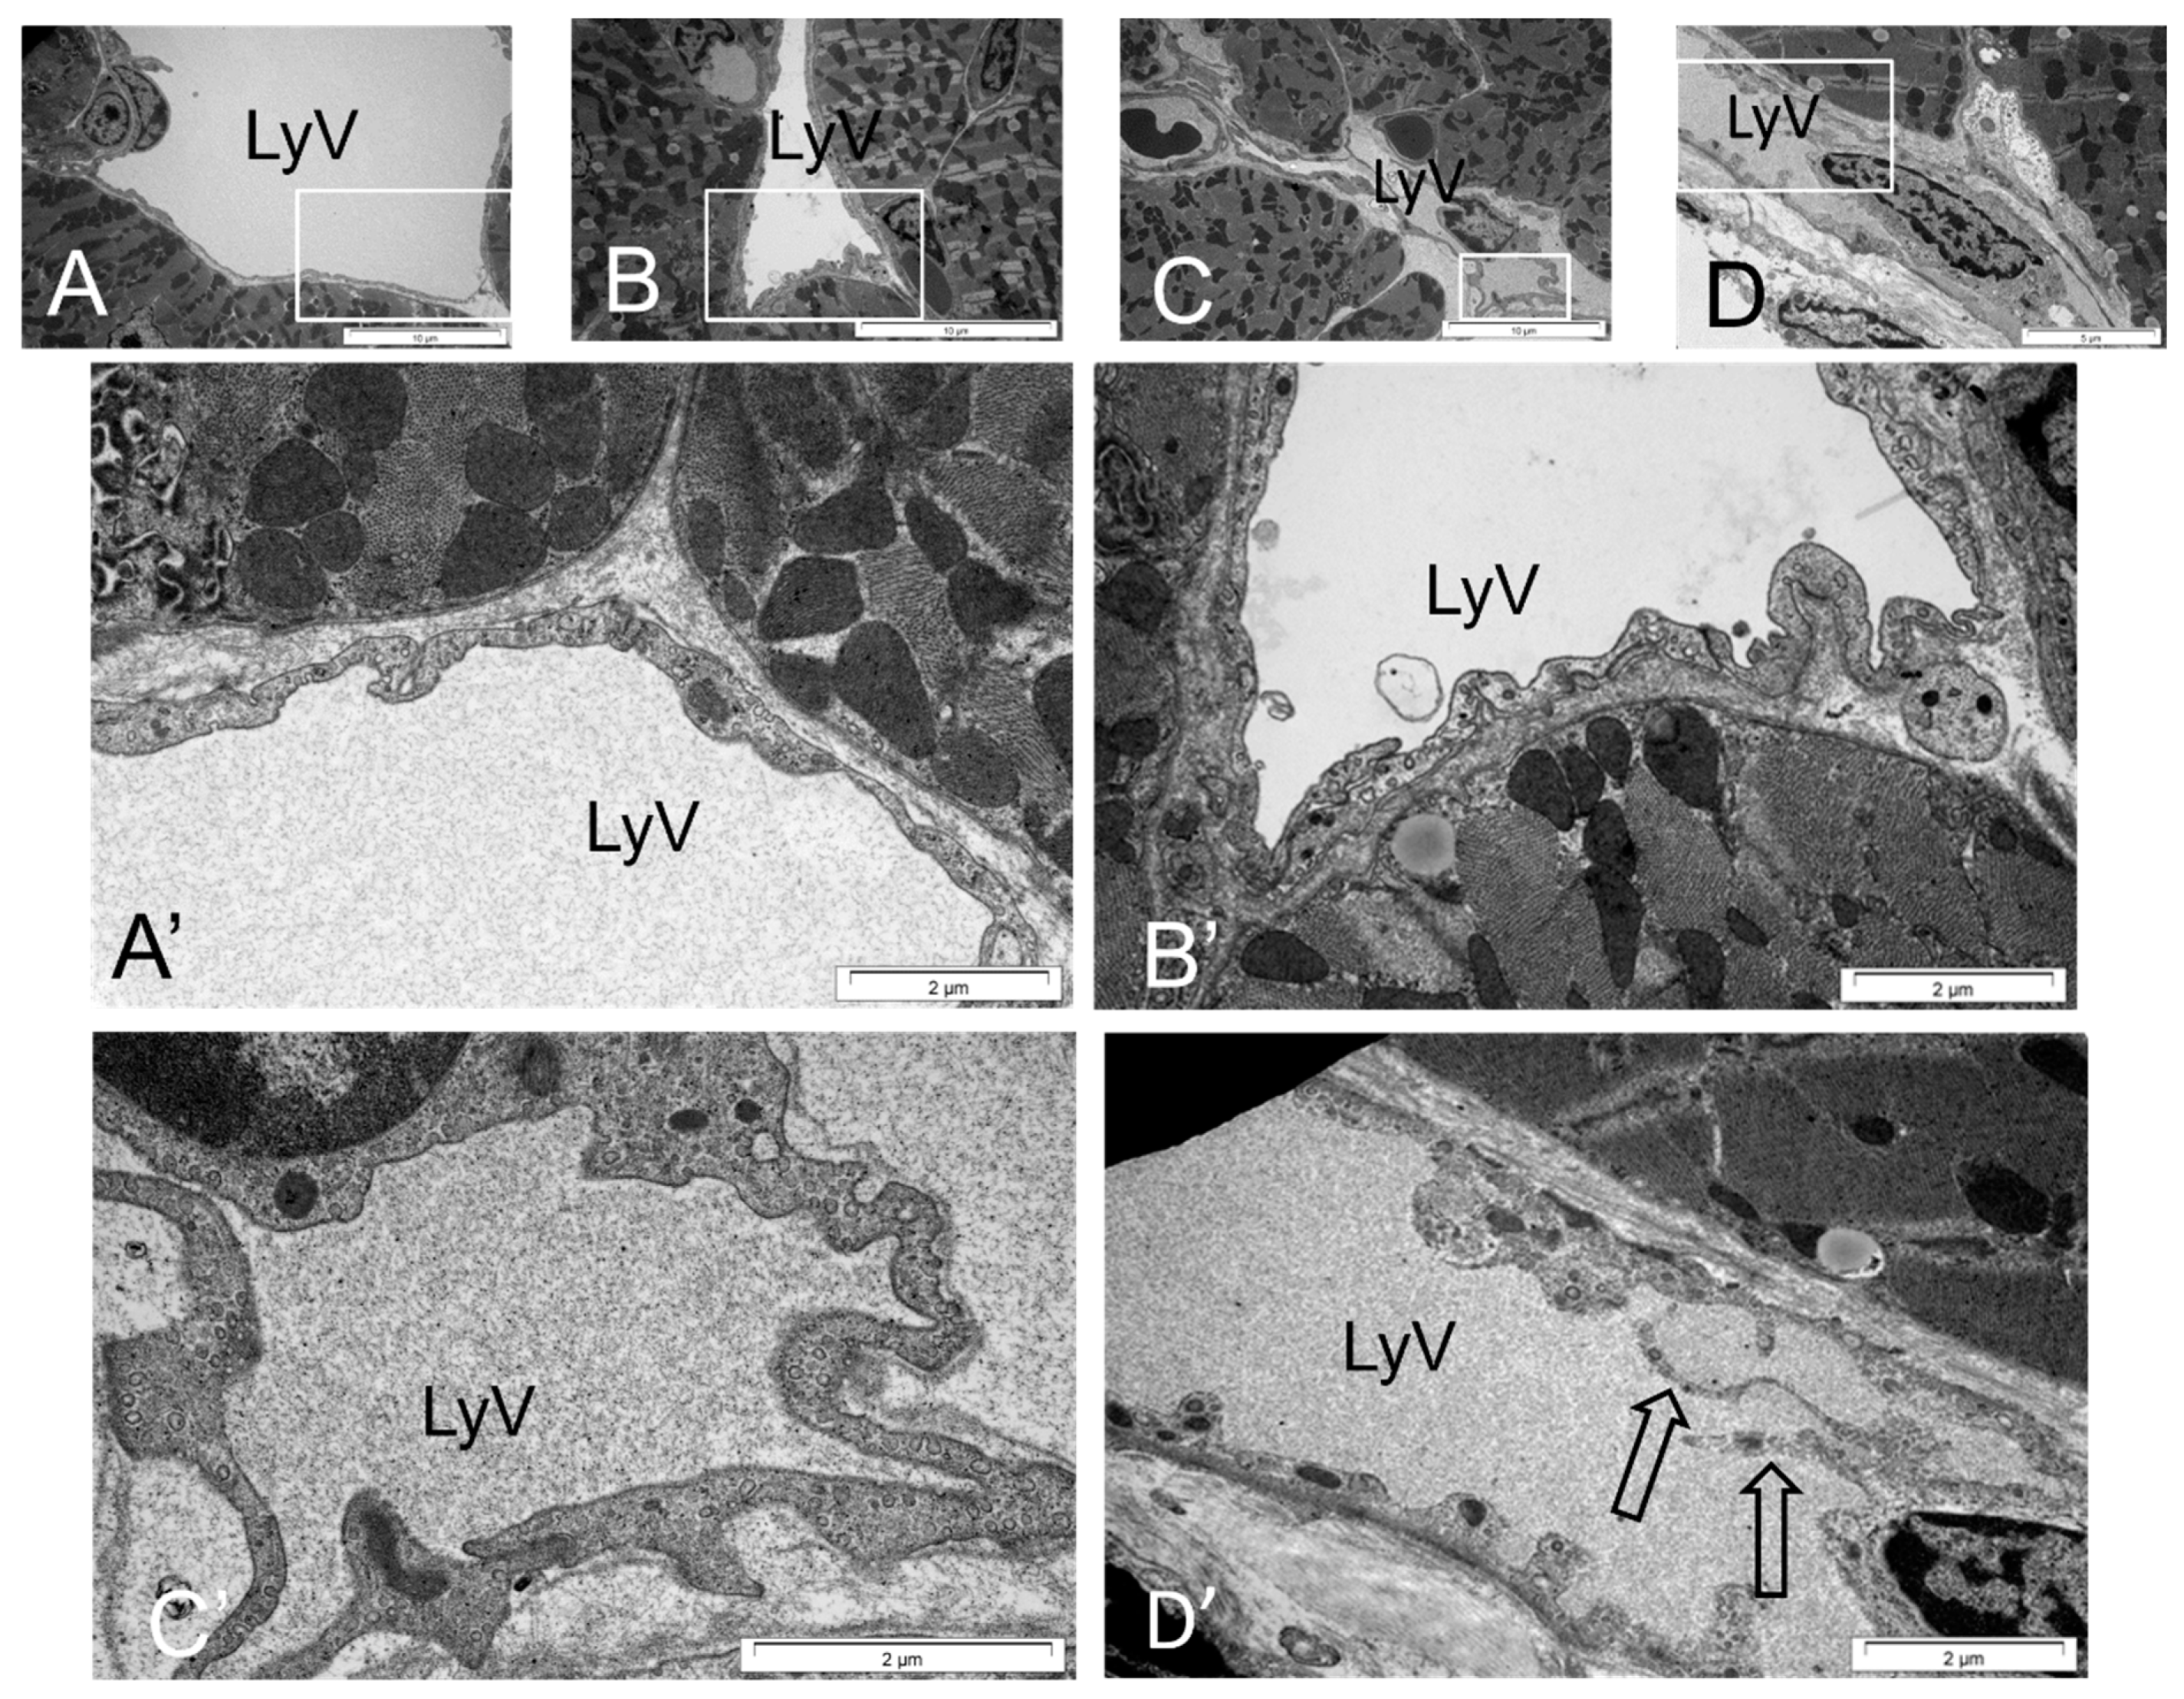

2.7. Ultrastructure and Morphometric Analysis

4.4. LyV Remodeling Is Part of Cardiac Remodeling